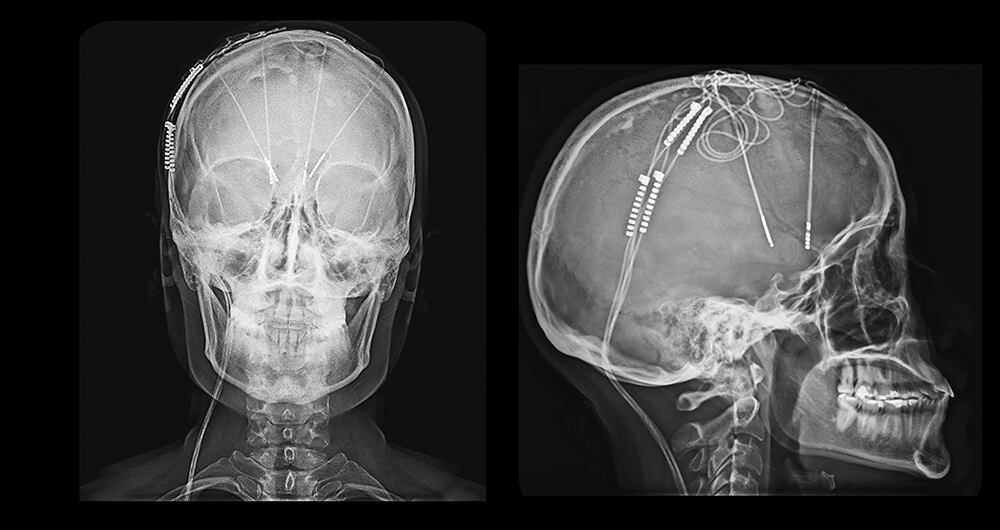

Lo innovador en el caso de Lorena, según le contó el doctor Contreras a SEMANA, fue que, a diferencia del procedimiento convencional que utiliza dos electrodos, la cirugía de la joven combinó cuatro electrodos.

En el caso de Lorena, se utilizó tecnología de última generación con un marcapaso cerebral de cuatro puertos y diseños combinados de chips con control independiente de corriente por contacto. “Esto permitió modular redes distintas, pero interconectadas, que intervienen en la tristeza, la culpa, la rumiación y la ansiedad, algo imposible con un solo electrodo por hemisferio”.

Sobre el procedimiento, Lorena asegura que estuvo consciente alrededor de seis horas, que fue la instalación de electrodos. “Después me sedaron para colocar el modulador en el pecho, como un marcapasos. En total, la cirugía duró entre diez y 12 horas. Salí a mi habitación casi a las nueve o 9:30 de la noche”.

Sobre la innovación en su procedimiento, asegura que “hasta ahora es el único caso documentado con cuatro electrodos en Colombia y posiblemente en el mundo. Independientemente de ser o no la primera, se trata de una innovación científica y humana. El doctor vino con ese enfoque científico de innovar en el procedimiento para estimular más áreas y mejorar el efecto terapéutico para quienes sufrimos de depresión y ansiedad”.